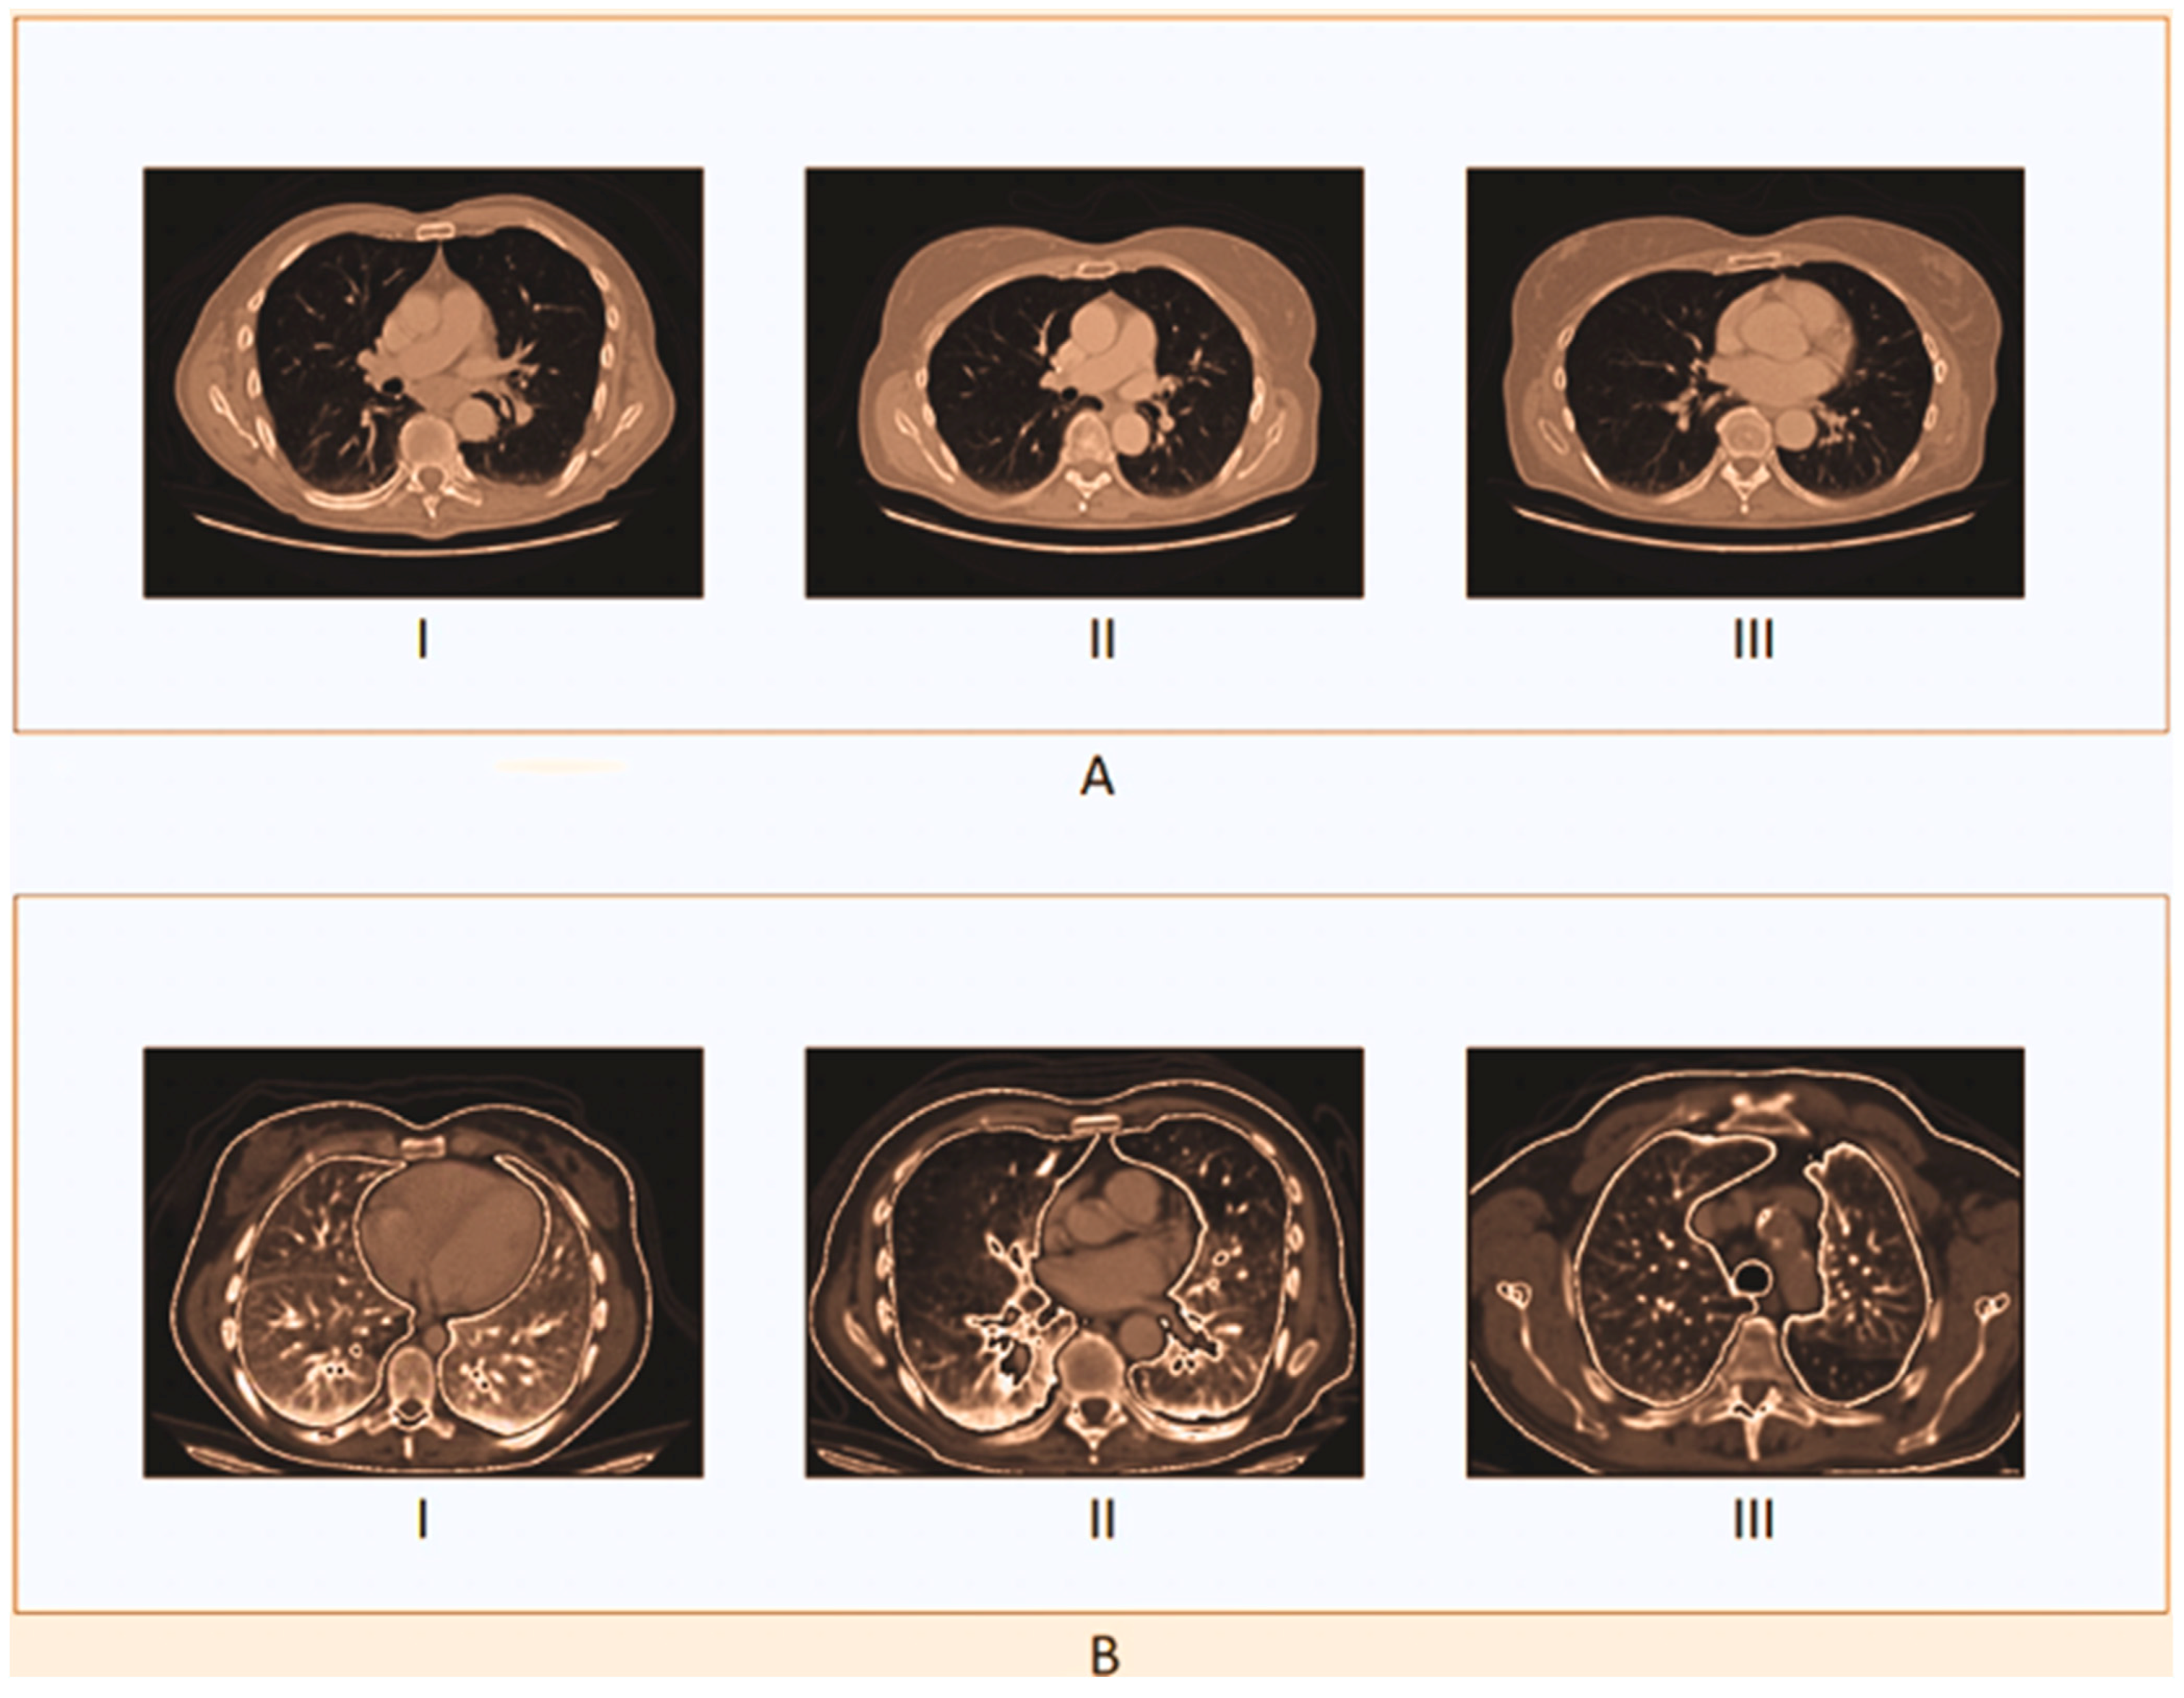

A single label—normal, large-cell carcinoma, or squamous cell carcinoma—is assigned to each image in the dataset. Throughout the patients’ clinical care schedule, CT scans were performed. Before deep learning models were trained on the dataset, two board-certified physicians rated the diagnosis on the images. Additionally, to ensure that the grading work was performed accurately, a third expert assessed the dataset images. In both the training and test sets, there was a very unequal distribution of classes. In contrast to the training set, certain samples were included in the test set. To create the new training set, the training and test sets were combined, jumbled, and randomly ordered. Figure 3 displays images for cases of squamous cell carcinoma or normal or large-cell carcinoma.

Figure 3.

Dataset Utilization for Cancerous Image. (a) Large-Cell Carcinoma; (b) Squamous Cell Carcinoma.

Here, the sample image of the suggested methodology is shown in Figure 4. In Figure 4A, the original CT sample images are displayed. As can be seen in Figure 4B, the contrast-stretch applied to the input images is preprocessed to remove noise using RWICWM. Next, in the picture of Figure 4C, we see the edge enhancement image. After, in Figure 4D, we see segmentation. Finally, Figure 4E the classified output is large-cell cancer, squamous cell cancer [51], and normal (without carcinoma).

Figure 4.

Sample images in the proposed model. (A,B) The top and bottom images show the original CT sample images and the contrast-stretched images. (C,D) The top and bottom images show the edge enhancement image and segmentation. (E) The images show the classified output (large-cell cancer, squamous cell cancer, and normal).